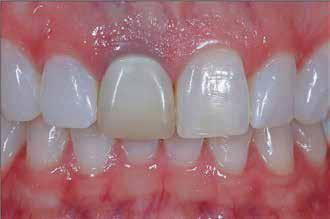

The prosthetic procedures for definitive restorations were performed 3 months after implant placement. The healing abutment was removed (Fig 10) scan body was placed in position and a digital implant-level impression was made using an intraoral scanner (Medit I 700 3D scanners) (16) (Fig 11,12)

Exocad was used to design the restoration (fig. 13) and was milled from a super translucent multilayered zirconia (KATANA Zirconia STML; Kuraray Noritake). The milled restoration was cemented on the Ti-base with a resin cement (RelyX Unicem; 3M ESPE). Then, the definitive restoration was connected to the implant, and the Ti-base screw was tightened to 20 Ncm according to the manufacturer’s instructions. The screw access channel was sealed with sterilized PTFE and photopolymerized composite resin (Filtek Supreme Ultra; 3M ESPE). The definitive restoration was evaluated for centric and eccentric occlusal contacts and then finished and polished (fig 14,15).

tissue during the healing period in one-step recording direct from the source and ensured this measurement protocol is more accurate than the conventional step which cumulates routine error in the impression taking with weight material, the poured stone model and hand-manual measuring. The use of CAD/CAM technology in implant crown design has the potential to improve the accuracy and e ciency of the restoration process, providing patients with a functional and aesthetic solution to their dental needs24 Healthy peri-implant gingiva is important to ensure a good emergence profile, particularly in the esthetic zone. It plays a role in preventing periimplant disease by forming a barrier to e ciently protect underlying bone and prevent access to microorganisms. In addition, after the final restoration, time may be required for soft tissue to fill the embrasure, which is more predictable with healthy tissue, shows adequate interdental papilla, well contoured gingiva, and the presence of stippling and no inflammation, indicative of healthy peri-implant tissue25